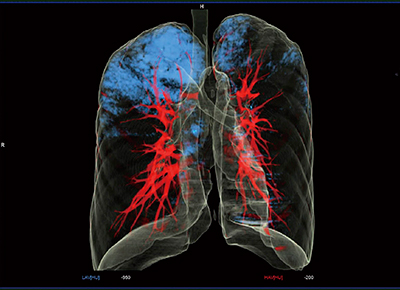

近年の肺野領域の健診において,もうひとつ重要なのが肺気腫の評価である。syngo.viaに最近搭載された肺気腫の定量化のためのアプリケーションであるPulmo 3Dにて評価した症例を示す。

症例4は,39歳,男性。喫煙歴19年,健診にて咳などの症状を訴えていた。スパイロメトリでは,肺活量(%VC)が119%で問題はなく,1秒率がやや低い72%であったが,CT画像上,経年変化は見られなかった。Pulmo 3Dでは,閾値を設定して3D画像を作成し(図6),肺気腫の指数をパーセントで表している(図7)。分葉ごとにその数値が示され,本症例では右肺上葉(UR)に最も多く低吸収域が認められた。

このように,syngo.viaでは肺気腫を定量化して経過観察を行うことも可能であり,今後,臨床応用の広がりが予想される。

図6 症例4:Pulmo 3Dによる肺の3D画像作成

図7 症例4:Pulmo 3Dによる肺気腫の定量化